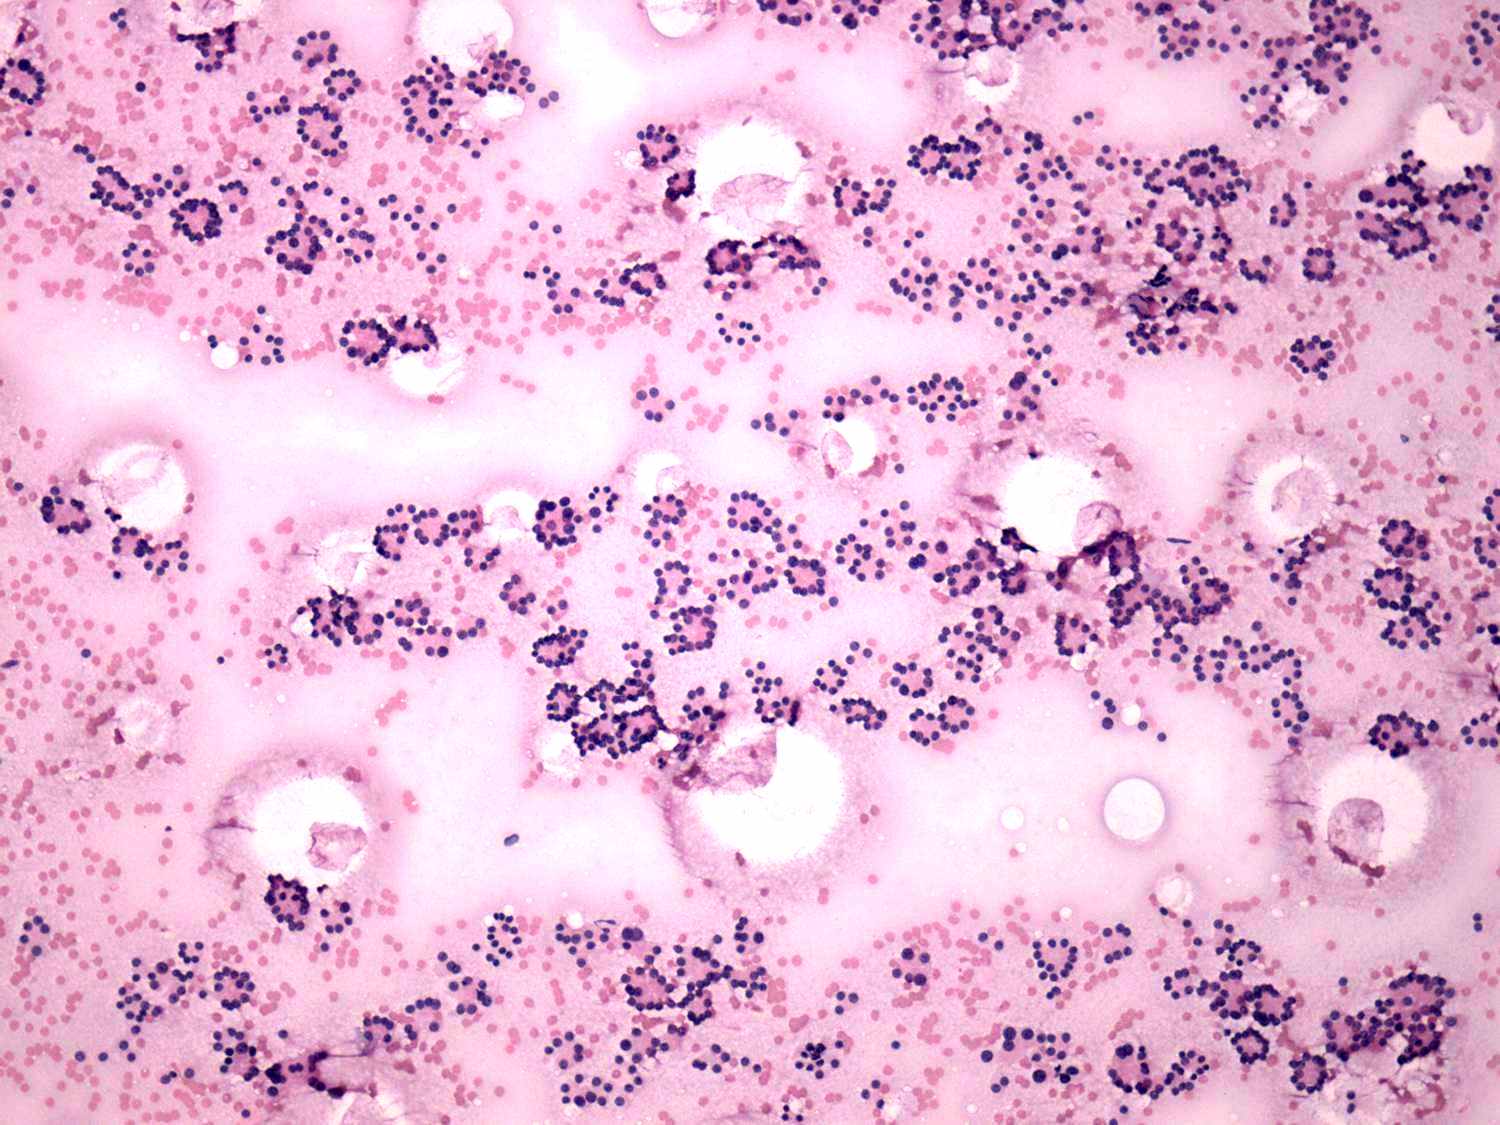

Follicular carcinoma - case 3

Both cases present a microfollicular proliferation. There were several atypical cells in the right case which increased the likelihood of malignant variant of follicular carcinoma.

The right case is even more edifying. Such pattern, i.e. no. colloid in the background, the arrangement of cells almost exclusively in micro- and normofollicles, the monomorphous pattern, the presence of prominent nucleoli, had to be a follicular tumor. However, the nodule proved to be not a follicular tumor but a hyperplastic nodule. This happens in around 10 to 15% of such patterns. If we take the ultrasound presentation into account around half of patients with such cytological presentation can be avoid unnecessary surgery.